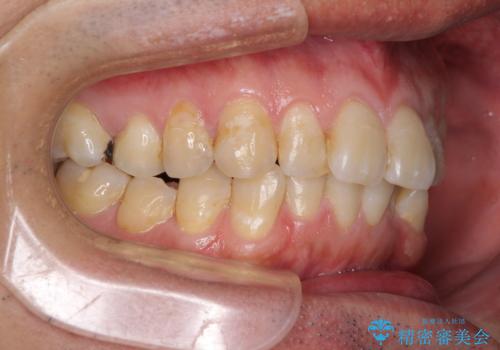

前歯のデコボコと下顎の八重歯 インビザラインによる矯正治療

- 前歯のデコボコや八重歯を気にして来院された患者様です。

インビザラインを用いて、歯列を整えることとしました。

下顎前歯は後戻りを起こしやすいため、舌側を細いワイヤーで固定し、マウスピース型リテーナーで保定を行うこととしました。